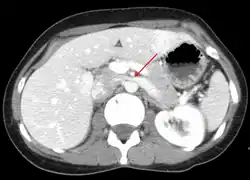

Nutcracker syndrome is diagnosed through imaging such as doppler ultrasound (DUS), computed tomography (CT) with contrast, magnetic resonance imaging (MRI), and venography.[12] The selection of the imaging modality is a step-wise process. DUS is the initial choice after clinical suspicion based on symptoms. However, often vascular compressions can be missed and CT with and without contrast is needed to visualize the vascular structures. MRI can be used if CT is not assessable. Venography with IVUS is gold standard for diagnosing.[12]

CT and MRI

CT and MRI with contrast can be used afterward to confirm compression by the AA and SMA with comprehensive measurements of the abdominal vasculature. A "beak sign" can often be seen in CT scans due to the LRV compression. However, CT and MRI cannot demonstrate the flow within the compressed vein. These two modalities can be used to confirm other evidence for NCS such as back-up of blood flow into the ovarian veins.[11][6]